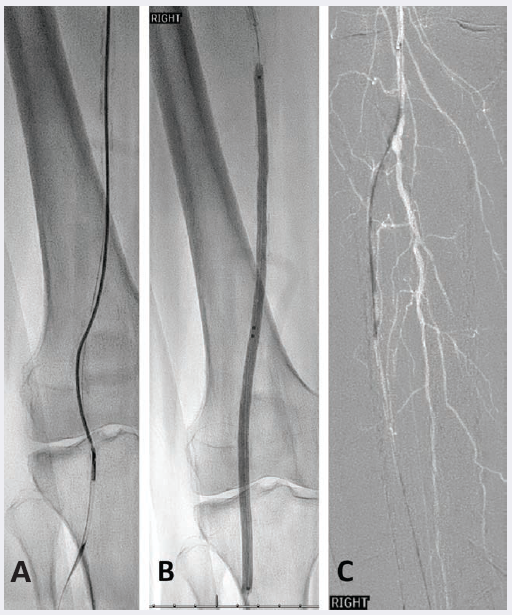

Ultrasound-guided access of the left common femoral artery was obtained and a right lower extremity angiogram was performed, demonstrating tandem distal superficial femoral artery (SFA) stenosis greater than 75% and 50% stenosis of the popliteal artery (Figure 1A). Below the knee there were tandem chronic total occlusions (CTO) of the mid and distal peroneal artery with dominant posterior tibial runoff, a distal occlusion at the level of the malleolus, and a distal anterior tibial artery occlusion without reconstitution of the dorsalis pedis artery (Figure 2A-B).

Selective angiogram of the distal posterior tibial artery with distal occlusion (B). 2 mm balloon

angioplasty of the distal posterior tibial and medial tarsal artery (C) with recanalization (D).

A 6 French 45 cm Pinnacle Destination sheath (Terumo) was seated in the proximal right SFA. An .035-inch Glidewire advantage (Terumo) and TrailBlazer support catheter (Medtronic) system traversed the SFA stenoses and a 5.0 mm SpiderFX Embolic Protection Device (Medtronic) was seated in the below-knee popliteal artery. A HawkOne M directional atherectomy system (Medtronic) was passed a total of 6 times in the distal superficial femoral and popliteal arteries for plaque remodeling and vessel preparation. Plain balloon angioplasty was performed in the popliteal and superficial femoral arteries. After confirmation of no dissections and resolution of stenosis, the segment was treated with drug-coated balloon angioplasty using the IN.PACT Admiral drug-coated balloon. The distal embolic protection device was removed.

An .014 wire was used to cross the posterior tibial artery CTO into the medial plantar artery. Angioplasty was performed using a 2.0 mm balloon with recanalization to the plantar artery (Figure 2C). Completion angiography demonstrated a widely patent SFA, popliteal artery (Figure 1C), and posterior tibial artery with inline flow to the medial tarsal artery (Figure 2D).

Follow-up arterial duplex ultrasound at 6 weeks showed biphasic waveforms throughout the SFA, popliteal, anterior tibial and posterior tibial arteries, and previously demonstrated peroneal artery occlusion. There was no hemodynamically significant stenosis visualized in the treated segments and non-compressible ABIs. The patient subsequently underwent a right 2nd and 3rd toe amputation for osteomyelitis, and on follow-up there was a granulating wound bed without residual infection.